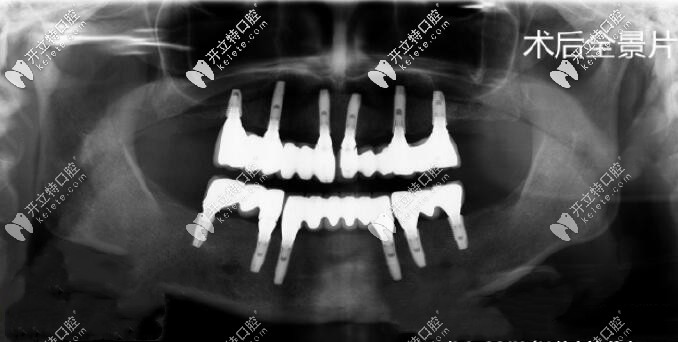

戴了1年零3個月的牙套終于要拆了,牙齒也比起以前整齊美觀了很多,心情很興奮但是又很不安。希望還在觀望的各位不要考慮那么多了,資金允許的情況下趁早去做矯正吧,不要再拖了,畢竟歲月不饒人??!